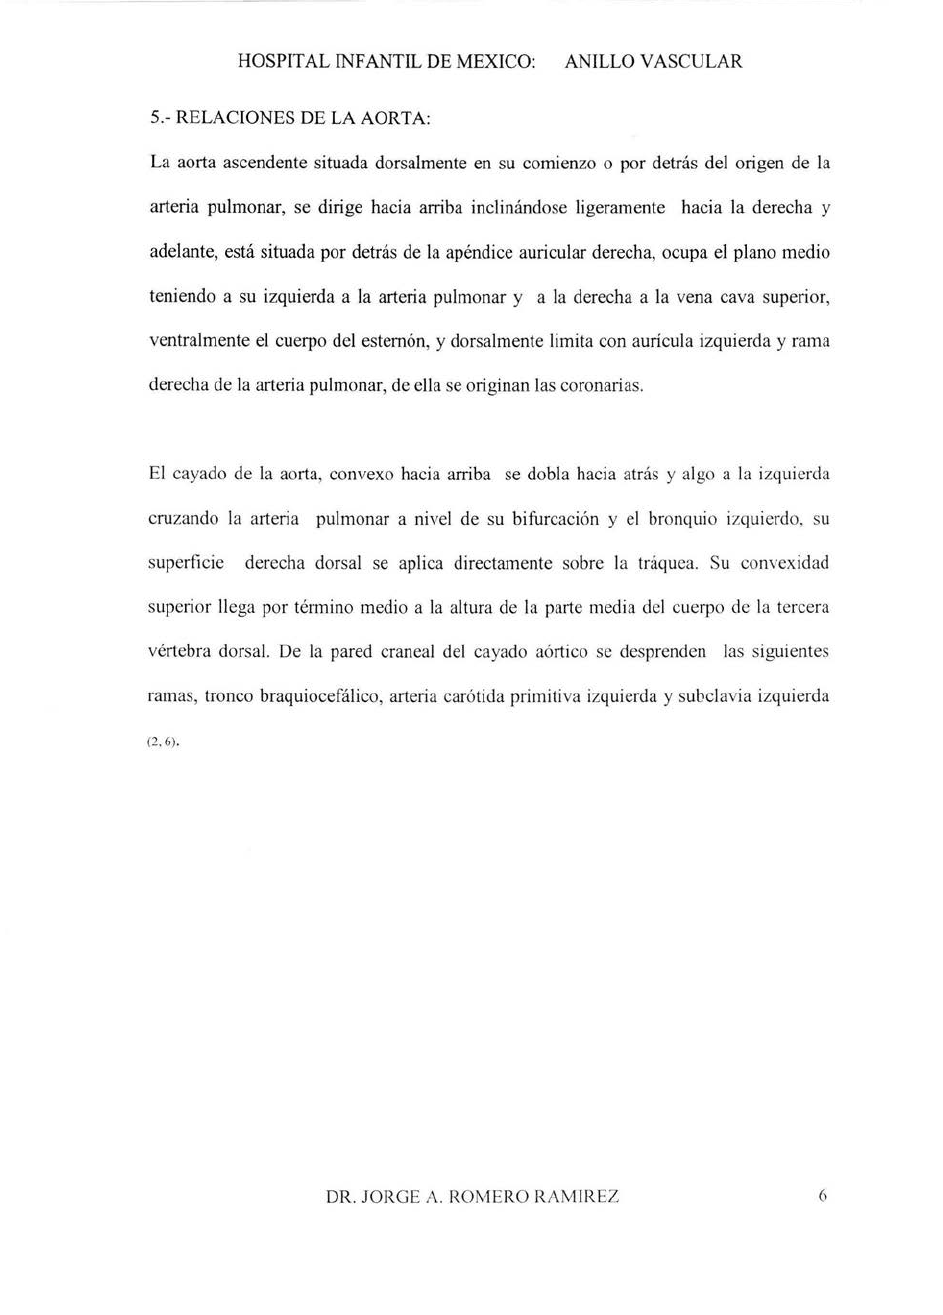

Anillo vascular MedlinePlus enciclopedia m dica illustraci n best sale, Anillos vasculares best sale, Anillos vasculares best sale, Anillo vascular. Web de las cardiopat as Cong nitas best sale, Anillos vasculares best sale, Anillos vasculares best sale, Caracter sticas y manifestaciones cl nicas de los anillos best sale, Anillos vasculares best sale, ANILLOS VASCULARES EN PEDIATR A. PRESENTACI N DE 2 CASOS best sale, Anillos vasculares best sale, Figure 1 from Anillo vascular por doble arco a rtico sim trico best sale, Anillos vasculares Radiolog a PPT best sale, Caso cl nico. Anillos Vasculares best sale, Anillo vascular por doble arco a rtico sim trico. Reporte de un caso best sale, PDF Anillo vascular completo diagn stico prenatal de doble arco best sale, VASCULAR RINGS MAGNETIC RESONANCE FINDINGS best sale, Anillos Vasculares y Slings PDF PDF Aorta Tos best sale, PDF S ndrome de Rubinstein Taybi asociado a anillo vascular best sale, Anillo vascular 15 anos de experiencia en el Hospital Infantil de best sale, Diagn stico y tratamiento de persistencia de cuarto arco a rtico best sale, Anillo vascular por doble arco a rtico sim trico. Reporte de un caso best sale, Reparaci n de sling de la arteria pulmonar sin necesidad de bypass best sale, PDF Anillos vasculares obstrucci n de v a a rea en ni os. Serie best sale, Figure 2 from Anillo vascular por doble arco a rtico sim trico best sale, Anillo vascular 15 anos de experiencia en el Hospital Infantil de best sale, Anillos vasculares completos Anales de Pediatr a best sale, ANILLOS VASCULARES HALLAZGOS POR RESONANCIA MAGN TICA best sale, Los Anillos vasculares Una amenaza creciente para la v a best sale, Anillo vascular por doble arco a rtico sim trico. Reporte de un caso best sale, Vascular rings and pulmonary arterial sling from respiratory best sale, Anillos vasculares nuestra experiencia en 18 casos best sale, Anillo vascular. Diagn stico por ecocardiograf a en periodo fetal best sale, Anillo vascular por doble arco a rtico sim trico. Reporte de un caso best sale, Figure 2 from Anillo vascular por doble arco a rtico sim trico best sale, Anillos vasculares y compresi n traqueo esof gica 15 a os de best sale, Figure 1 from Anillo vascular por doble arco a rtico sim trico best sale, Doble arco a rtico. Reporte y an lisis de caso en un paciente best sale, S ndrome de Rubinstein Taybi asociado a anillo vascular completo best sale, Multidetector Computed Tomography for Congenital Anomalies of the best sale, PDF Anillos vasculares como diagn stico diferencial del asma best sale, Anillos vasculares nuestra experiencia en 18 casos best sale, Anillos Vasculares y Slings PDF PDF Aorta Tos best sale, Vascular Rings Practice Essentials Anatomy Pathophysiology best sale, Multidetector Computed Tomography for Congenital Anomalies of the best sale, Resumen topografia miembro inferior Anatom a e Im genes best sale, Vascular Rings Practice Essentials Anatomy Pathophysiology best sale, Cardiopat as cong nitas. Anillo vascular best sale, Anillos vasculares completos Anales de Pediatr a best sale, Anillos vasculares y compresi n traqueo esof gica 15 a os de best sale, Multidetector Computed Tomography for Congenital Anomalies of the best sale.